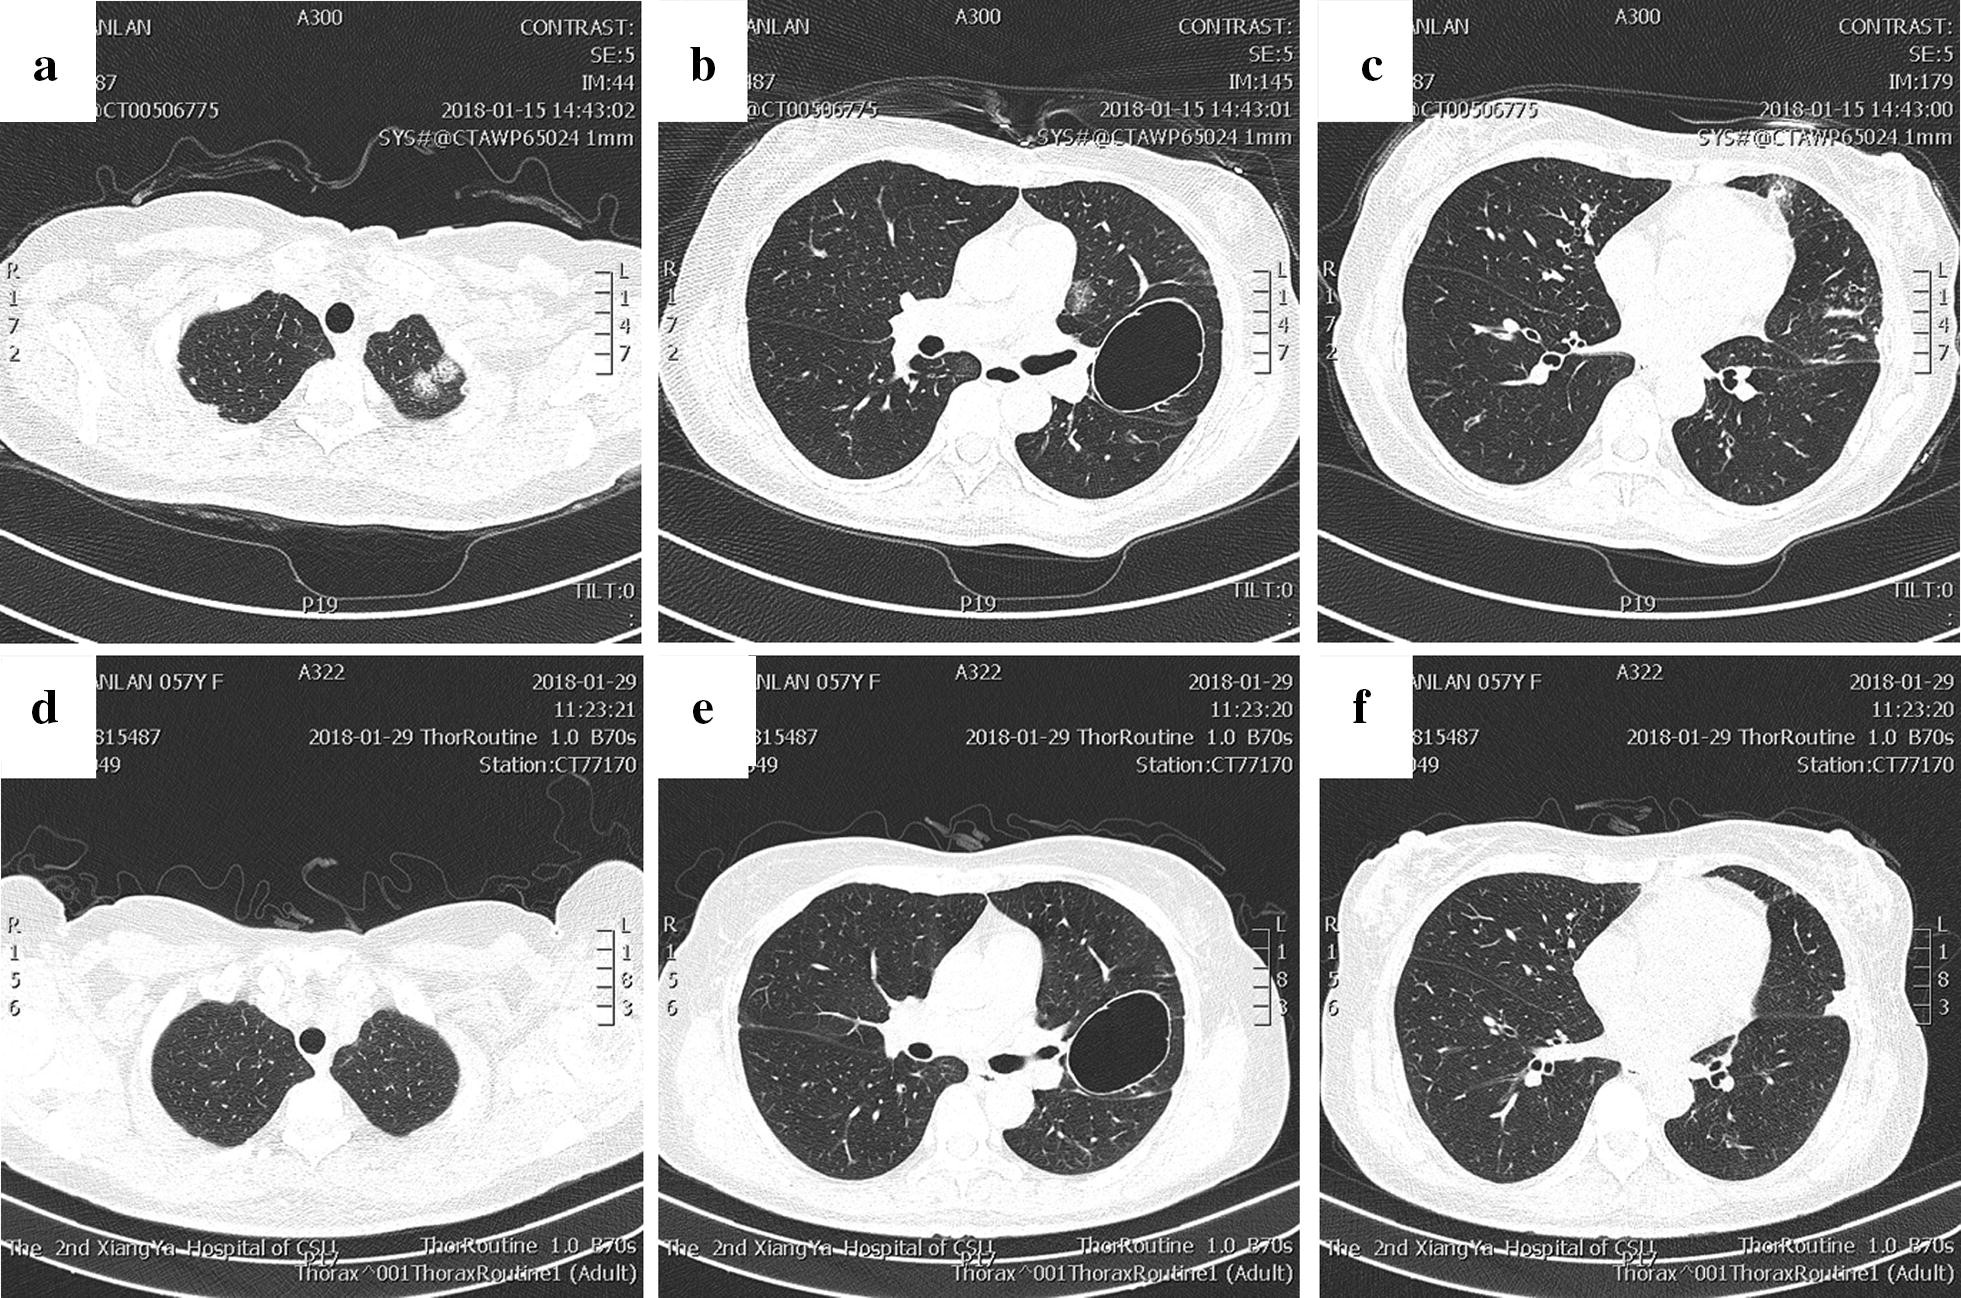

Fig. 5

Chest CT images. a–c Chest CT showed multiple infiltrates in the upper left lung and lower right lung and ground-glass opacities in the subpleural regions of both upper lung fields; d–f the lesion in the lower right lobe was partially absorbed